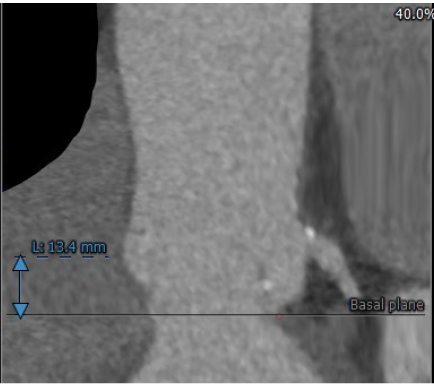

瓣环直径26.7

左室流出道直径:30.8

冠脉高度尚可。左冠高度:13.4,右冠高度:20.6。心脏角度52